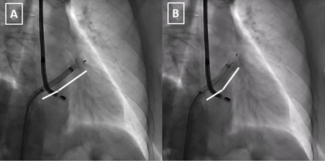

When dislodged stents remain on the coronary wire, the wire can be snared outside of the body. These two cases demonstrate the use of the presnaring technique to retrieve dislodged coronary stents when the stent remained on the coronary wire.